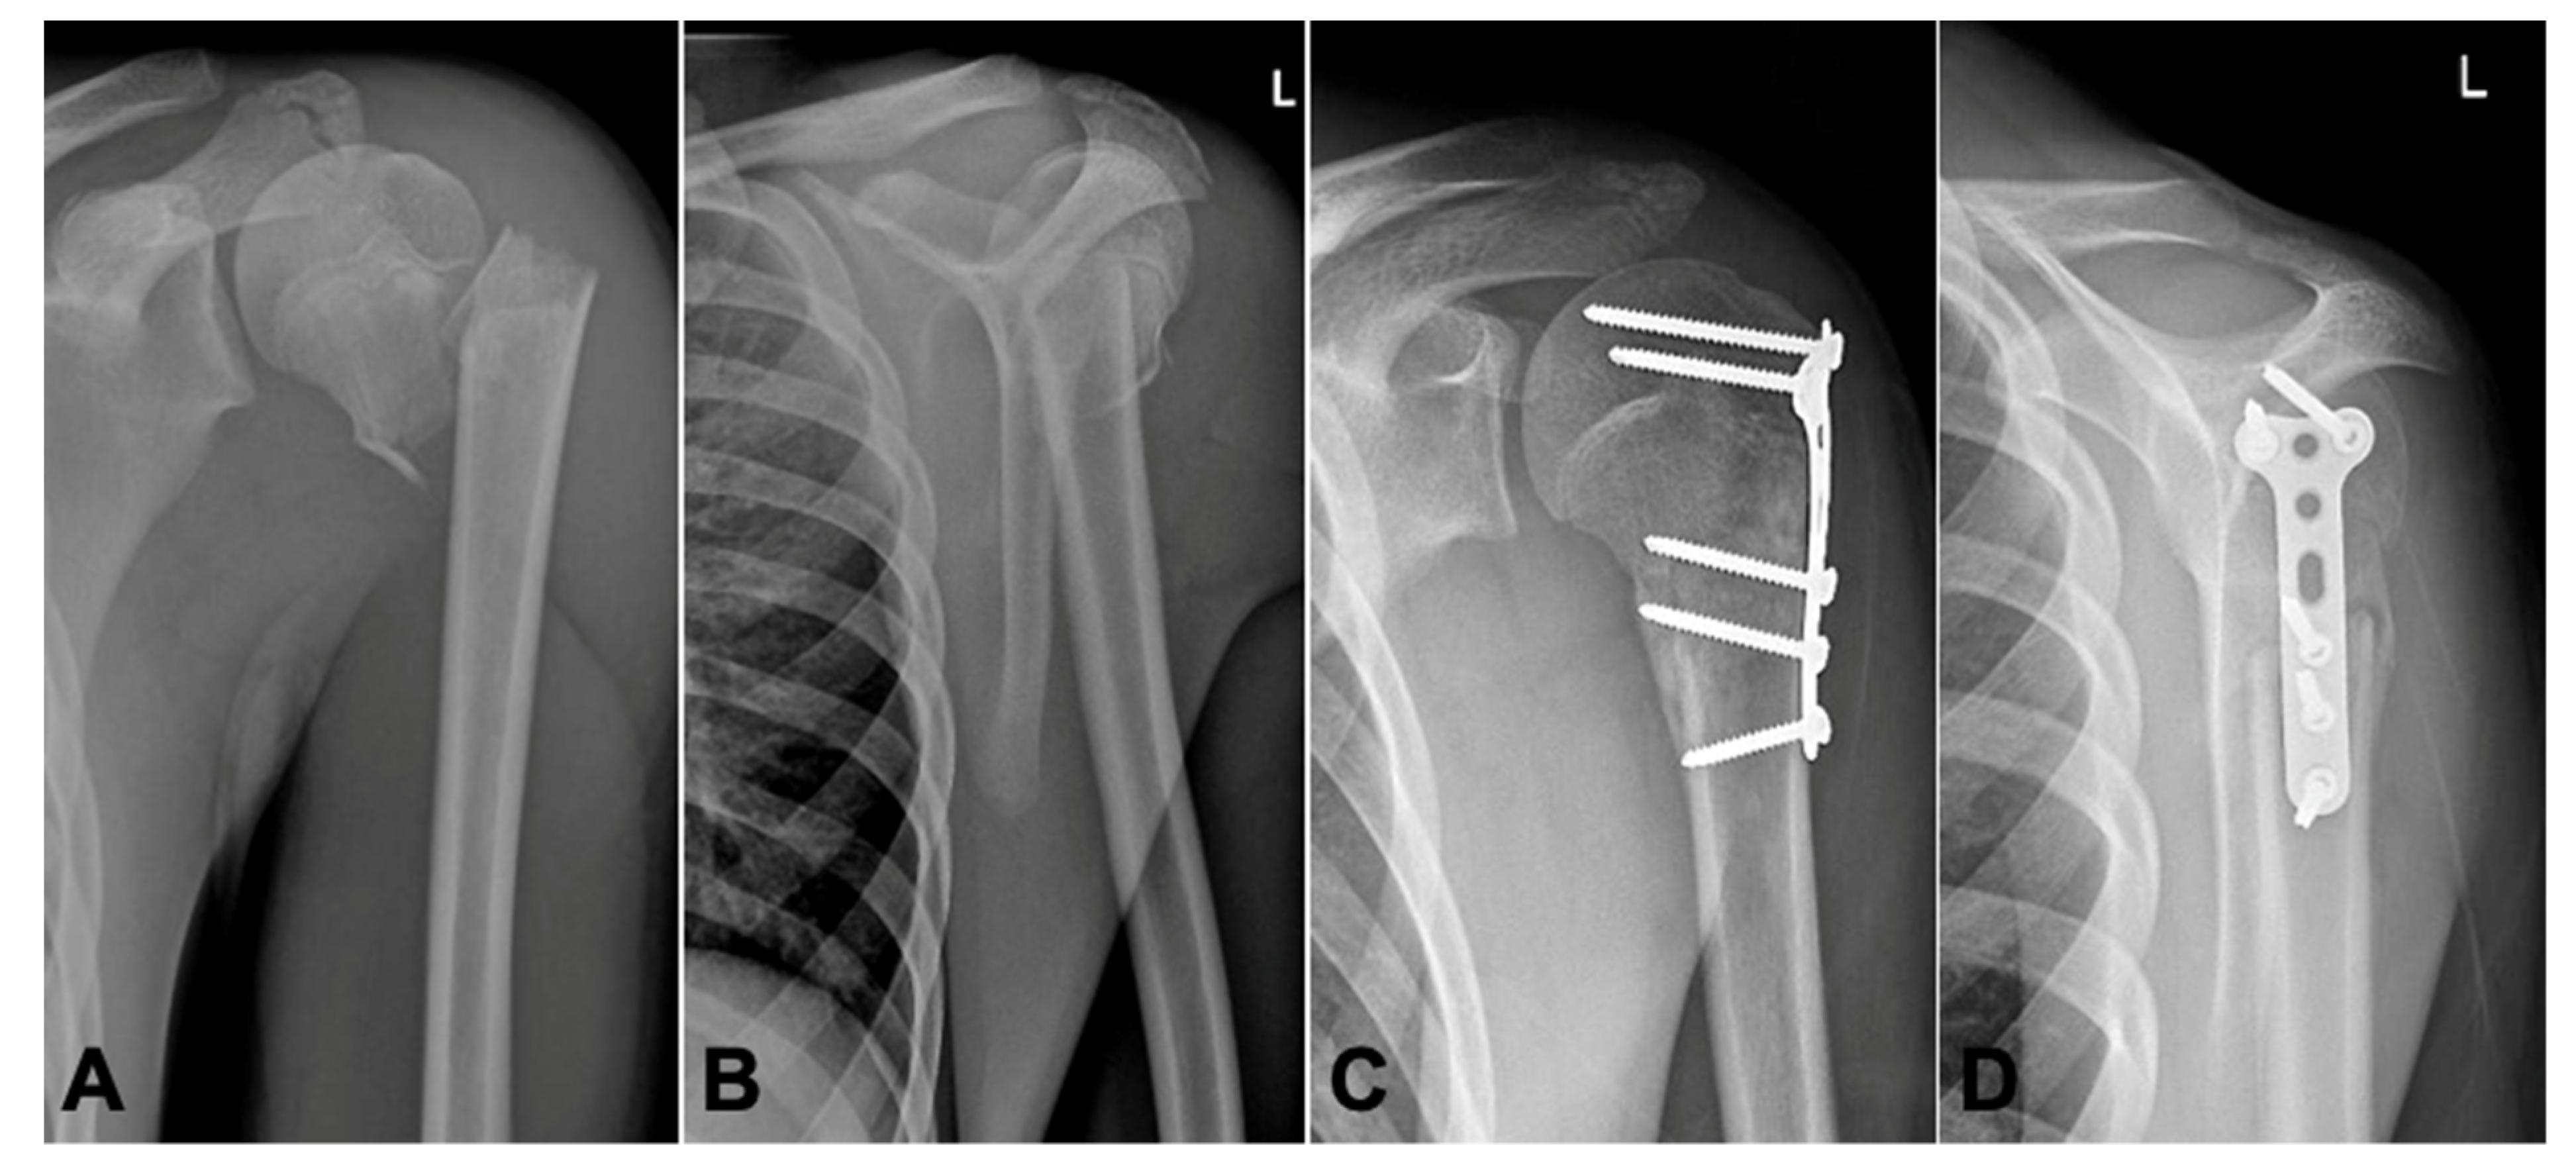

Muscular tension displaces the proximal fragment in varus and posteromedially, whereas the distal fragment moves anteriorly and in adduction (

Figure 1A,B).

There were five boys and one girl with a mean age of 14 years (8–16 years). At the time of injury, mostly accidents during physical activities which caused an isolated injury to the proximal humerus, all fractures were proximal metaphyseal fractures. Five patients had a Neer–Horwitz Grade III fracture and one had a Grade IV (patient N° 4, see

Table 1) completely displaced fracture of the proximal humerus (

Figure 1A,B). In these six patients, a closed reduction was attempted; in five patients, an immediate conversion to open surgery with open reduction and internal plate fixation was necessary.

All fractures showed advanced radiological healing at the 10–12 weeks follow-up (

Figure 1C,D). Postoperatively, there was no loss of reduction, residual deformity or screw migration.